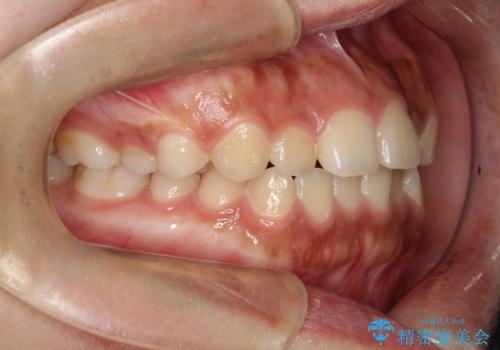

インビザライン 前歯のがたつきを目立たず矯正

- 前歯のがたつきが気になるとのことで来院されました。

インビザラインにて治療を行いました。

わずかに歯と歯の間に隙間を作り、歯列矯正を行いました。

マウスピースをしっかりと使用していただけたので、スムーズに治療を終了することができました。